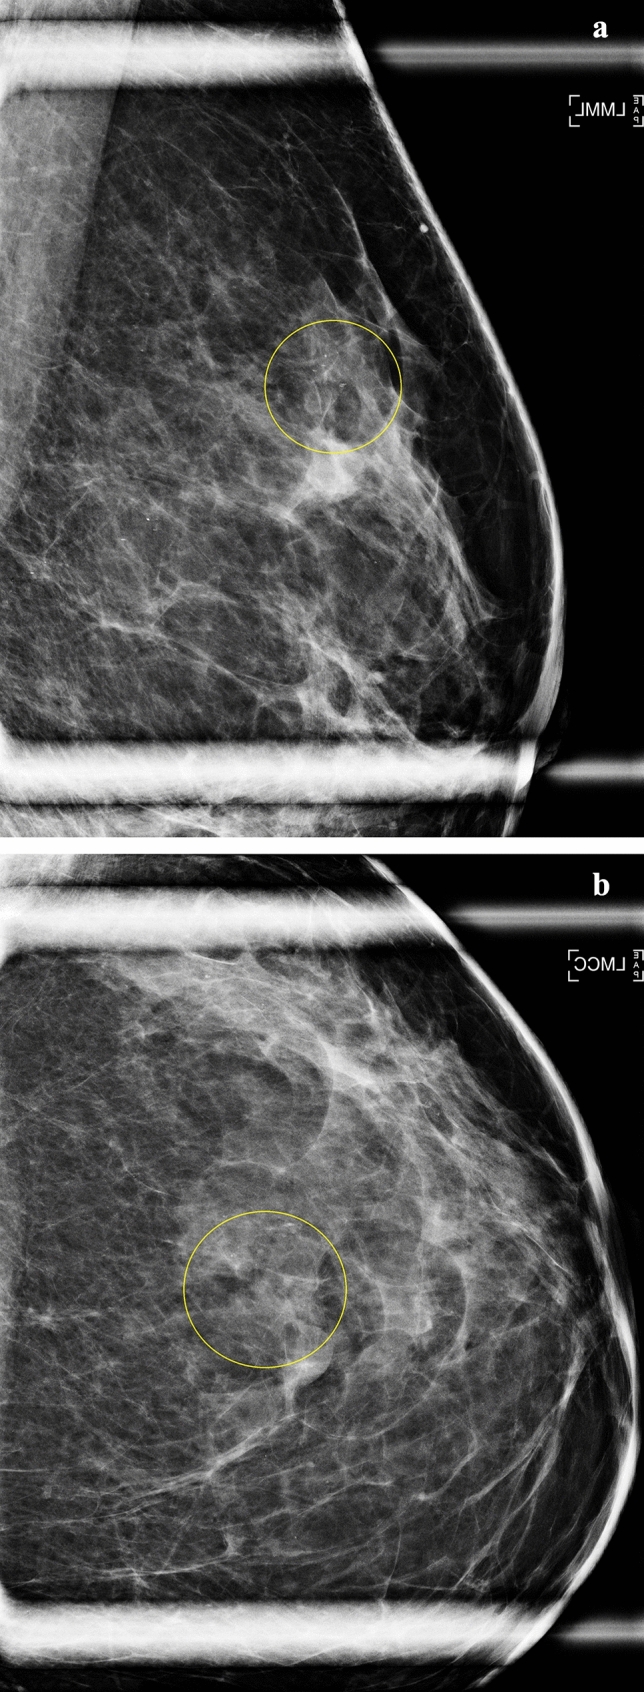

Purpose: Mammographic calcifications on mammograms with a negative/benign assessment are associated with increased breast cancer risk. Associations with advanced breast cancer risk are unknown. We evaluated whether calcifications recorded on mammography reports are associated with advanced invasive breast cancer risk.

Methods: We included 3,710,313 screening mammograms with a negative/benign final assessment performed on 991,991 women aged 40-74 in the Breast Cancer Surveillance Consortium associated with 7229 advanced cancers. We calculated cumulative 5-year advanced (prognostic pathologic stage ≥II) breast cancer risk and hazards ratios (HR) adjusted for clinical risk factors according to presence or absence of calcifications by menopausal status, dense (heterogeneously or extremely dense) vs. non-dense (almost entirely fatty or scattered fibroglandular density) breasts, body mass index (BMI) < 25 kg/m2 vs. ≥ 25 kg/m2.

Results: Prevalence of calcifications was 6.1% among women who developed advanced breast cancer vs. 3.6% among others. Overall associations of advanced cancer with calcifications were similar for premenopausal (HR = 1.4; 95% CI 1.1-1.9) and postmenopausal (HR = 1.5; 95% CI 1.2-1.7) women. Compared to postmenopausal women with non-dense breasts and BMI < 25 kg/m2 without calcifications [cumulative 5-year advanced cancer incidence = 1.6 (95% CI 1.3-2.0) per 1000 women], postmenopausal women with dense breasts, BMI ≥ 25 kg/m2, and calcifications had 5.5-fold (95% CI 3.9-7.7) higher advanced cancer risk [cumulative 5-year advanced cancer incidence = 10.2; (95% CI 7.0-13.3) per 1000 women]. Results were similar for premenopausal women.

Conclusion: Mammographic calcifications increase advanced cancer risk beyond having dense breasts and being overweight/obese. Future research should investigate strength of associations by type of calcification and incorporation of calcifications into advanced cancer risk models for improvement in model accuracy.